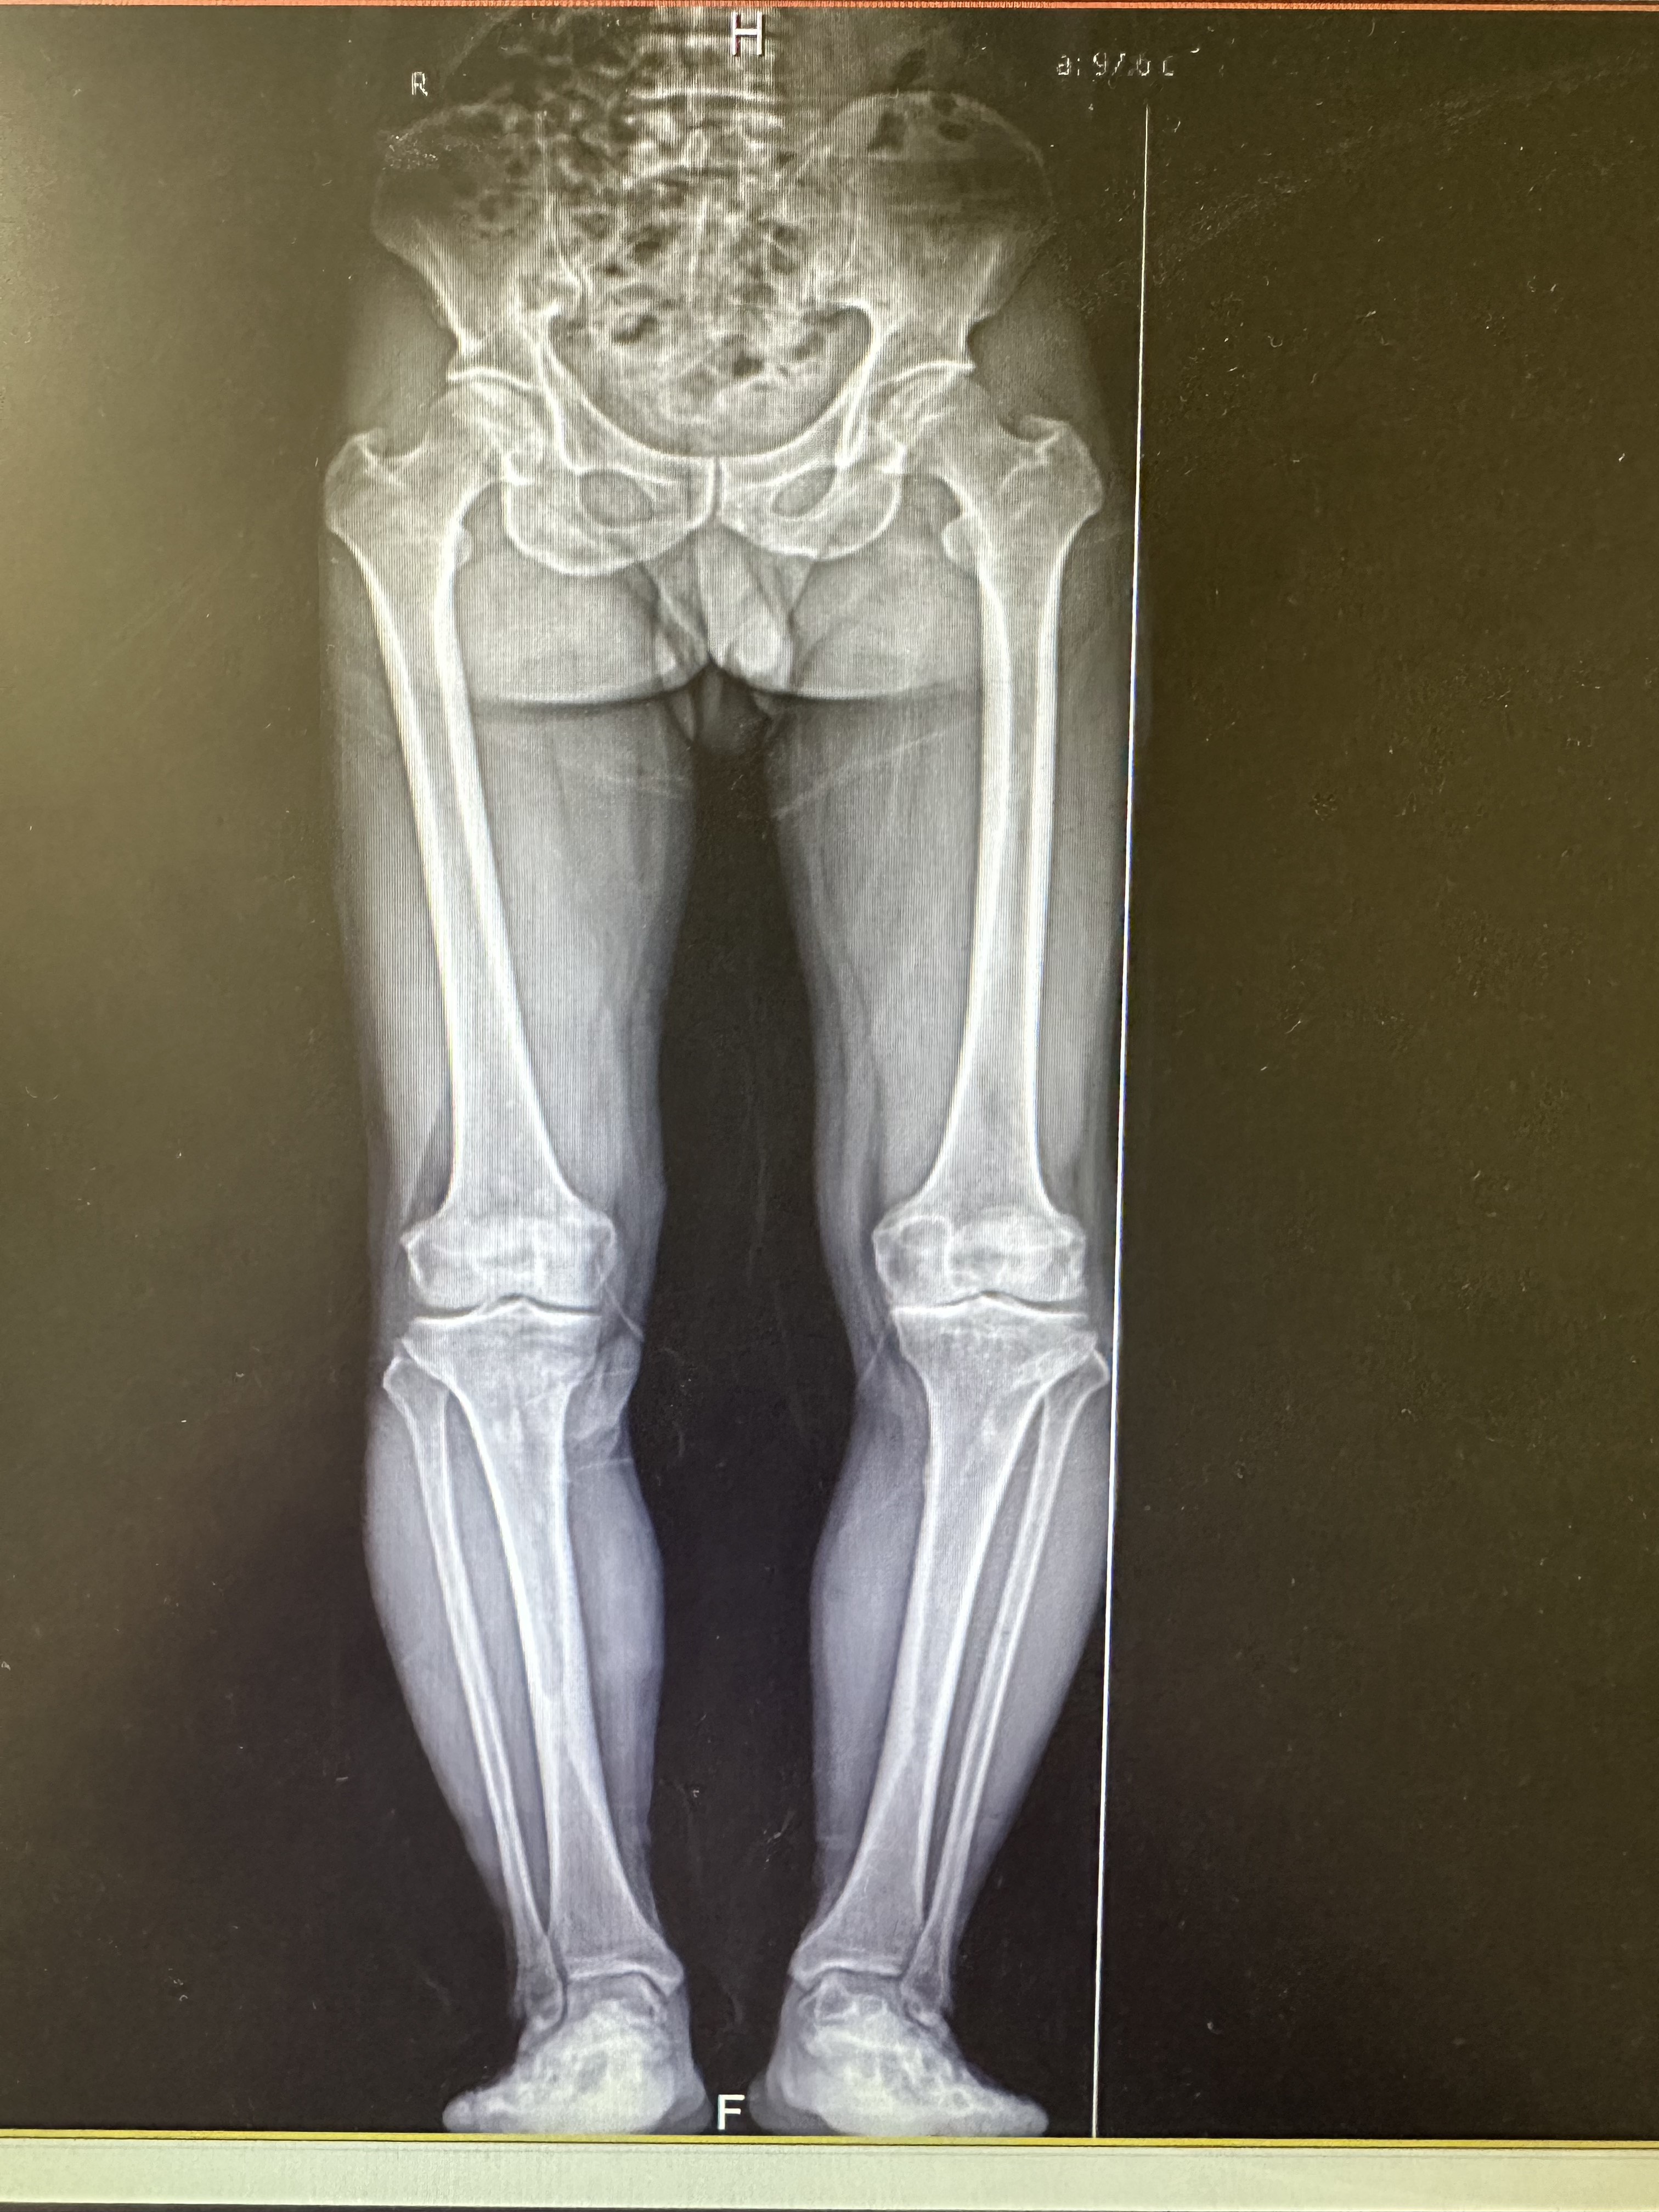

這可能是足部旋轉(zhuǎn)異常的信號(hào),俗稱足內(nèi)八或在八,它不僅僅是走路姿勢(shì)問(wèn)題,如果不及時(shí)矯正可能會(huì)影像孩子未來(lái)的骨骼健康和運(yùn)動(dòng)能力。足內(nèi)八(足內(nèi)旋狀態(tài)):走路時(shí)腳尖向身體中線方向旋轉(zhuǎn)。足外八(外旋步態(tài)):走路時(shí)腳尖向身體外側(cè)旋轉(zhuǎn)。原因可能在哪?問(wèn)題可能出在腳本身、小腿脛骨或者大腿股骨的旋轉(zhuǎn)角度異常等。嬰幼兒期(尤其1-3歲學(xué)步期),輕度內(nèi)八(前腳掌內(nèi)、外側(cè)緣與縱軸形成的夾角不超過(guò)5度)很常見(jiàn),很多是發(fā)育過(guò)程中的正常現(xiàn)象,不部分會(huì)隨著成長(zhǎng)自然改善。外八字相對(duì)少見(jiàn)一些,但也非罕見(jiàn)。出現(xiàn)一下情況,家長(zhǎng)務(wù)必提高警惕,及時(shí)尋找專業(yè)評(píng)估:年齡超過(guò)4~5歲,內(nèi)/外八字依然明顯兩邊腿腳不對(duì)稱,一側(cè)明顯比另一側(cè)嚴(yán)重越來(lái)越嚴(yán)重,而不是逐漸好轉(zhuǎn)。3~8歲是骨骼可塑性很強(qiáng)的關(guān)鍵時(shí)期專業(yè)醫(yī)生需要判斷孩子是暫時(shí)性的生理現(xiàn)象,還是存在需要處理的結(jié)構(gòu)性問(wèn)題。如果是結(jié)構(gòu)性問(wèn)題,黃金期進(jìn)行科學(xué)干預(yù)效果最好。起到減輕關(guān)節(jié)異常負(fù)荷,避免疼痛和更嚴(yán)重的骨骼肌肉問(wèn)題。早期、規(guī)范的矯正治療通常能獲得滿意效果,避免孩子將來(lái)可能承受手術(shù)之苦。

其實(shí),寶寶生下來(lái)就是O型腿,像青蛙一樣展開(kāi)下肢,O型腿是嬰幼兒時(shí)期生理現(xiàn)象。而且,嬰兒時(shí)期髖關(guān)節(jié)的屈曲外展位有利于髖關(guān)節(jié)的發(fā)育。大部分寶寶在嬰幼兒時(shí)期,都會(huì)經(jīng)歷O型腿的演變過(guò)程,這個(gè)是寶寶的正常發(fā)育。1歲以內(nèi):嬰幼兒腿部會(huì)成橢圓形,形狀類似青蛙腿或O型腿。1歲半以內(nèi):寶寶的腿逐漸開(kāi)始變直。3~6歲:有些寶寶的膝蓋會(huì)往內(nèi)撇,呈X型腿,但也有寶寶沒(méi)有這個(gè)階段。7歲:寶寶7歲左右,腿型才真正的確定和變直。寶寶腿為什么成O型腿?主要是由于在母體內(nèi),寶寶就是一種蜷縮的姿勢(shì),所以家長(zhǎng)不必過(guò)于擔(dān)心。什么情況下需要就醫(yī)?1、寶寶2歲后還是O型腿,8歲后還是x型腿而且越來(lái)越嚴(yán)重。2、寶寶兩條腿嚴(yán)重不對(duì)稱。3、寶寶如果腿彎曲的程度比較嚴(yán)重,那么考慮寶寶可能存在缺鈣,可以到醫(yī)院給寶寶完善相關(guān)方面的檢查,如果有缺失及時(shí)補(bǔ)充,平時(shí)多帶孩子參加戶外活動(dòng),多曬太陽(yáng),促進(jìn)皮膚,維生素D合成,促進(jìn)鈣吸收。3、怎么判斷寶寶存在O型腿和X型腿?放松寶寶雙腿,膝關(guān)節(jié)并攏時(shí),兩側(cè)踝關(guān)節(jié)之間距離超過(guò)6cm踝關(guān)節(jié)并攏時(shí),兩側(cè)膝關(guān)節(jié)之間距離超過(guò)6cm,則存在O型腿或X型腿的風(fēng)險(xiǎn),需要帶寶寶線下咨詢。